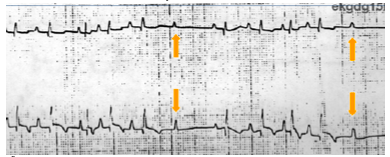

2nd degreee AV block

atrial fibrillation

Escape beat

ventricular premature beat

extrasystole

bigeminal rthythm

Ventrical fluttern